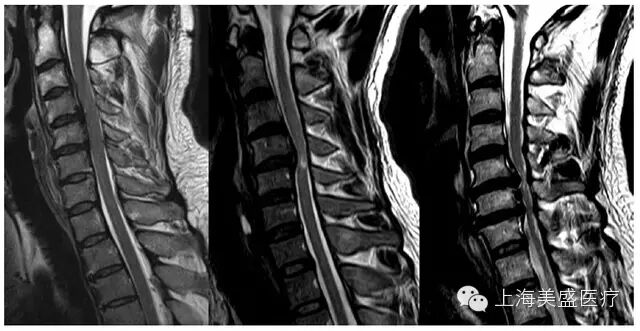

根据 MRI 矢状位 T2 相,将髓内高信号分为:0 级:无,1 级:局限于单个椎间盘水平;2 级:超出单个椎间盘水平(图 1)。

图 1 颈椎 OPLL 压迫致脊髓内高信号的 T2 相代表 MRI。左图:0 级,无脊髓内高信号;中间:1 级,脊髓内高信号,C4/5 椎间盘水平;右图:髓内高信号超过 1 个椎间盘水平。